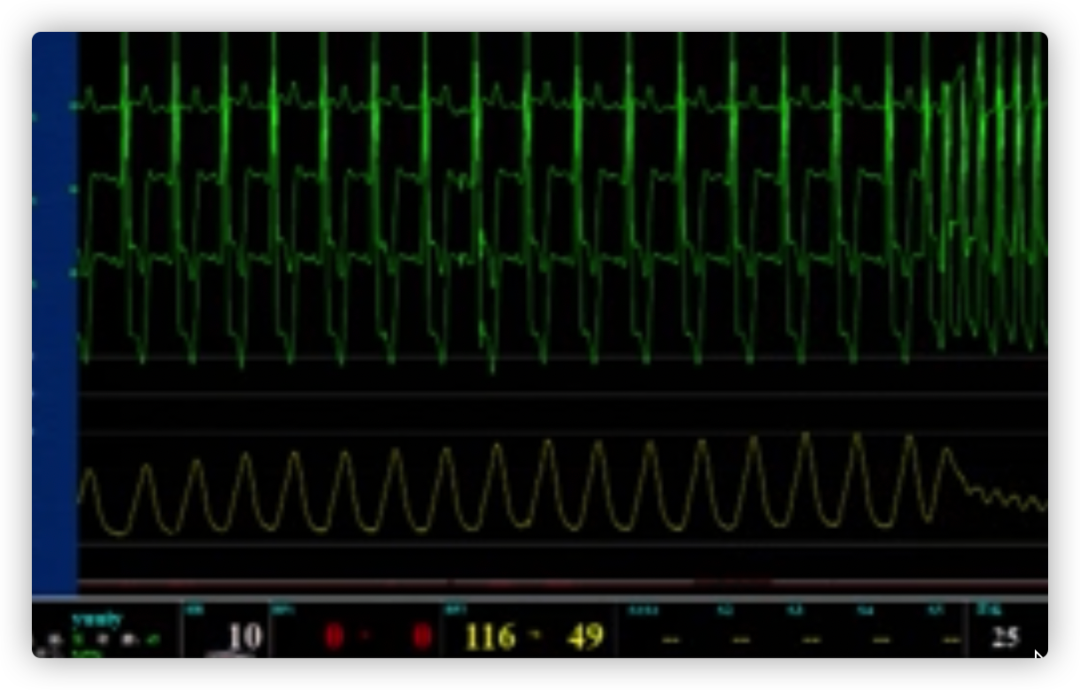

ECG术前

ECG术后即刻

ECG出院时